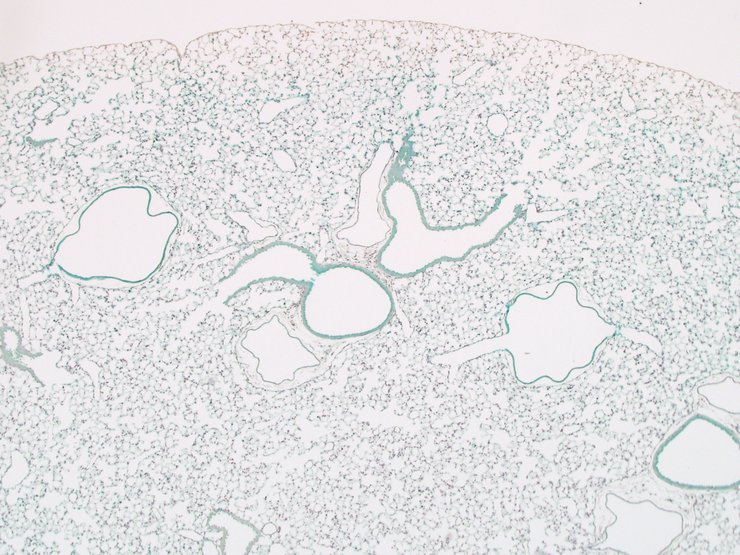

TS28: lung Present TCP_2460025

TS28: lung Present TCP_2460026